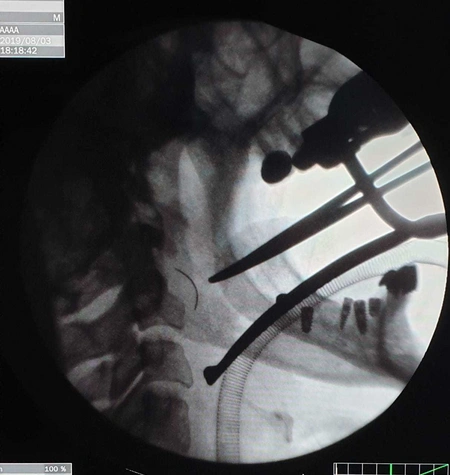

Как сообщает Report, хирург удалил фрагмент иглы длиной около 2 см, оставшийся в горле пациентки во время операции по удалению небной миндалины (тонзиллэктомия), проведенной десять лет назад.

По словам Э.Акбарова, тонзиллэктомия сама по себе непростая операция: "Но в большинстве случаях операцию проводят под местным наркозом и в несоответствующих амбулаторных условиях. Эта операция требует специальных навыков. Во время тонзиллэктомии в 2009 году у пациентки началось кровотечение из правого миндаликового ложа. Для остановки кровотечения было принято решение наложить швы на рану. Во время этой процедуры игла сломалась и сломанный фрагмент остался в мягких тканях шеи. Операция длится четыре часа, кровотечение останавливается, но сломанную иглу обнаружить не удается. В послеоперационный период у пациентки отмечались боли в правом отделе шеи, особенно при глотании и наклоне шеи. Но в то время в ходе радиологического обследования медицинскому персоналу не удалось выявить проблему, а пациентке сказали, что проблема является субъективной".

Хирург-оториноларинголог отметил, что инородное тело было обнаружено случайно: "Во время стоматологического осмотра с проведением компьютерной томографии в горле пациентки был обнаружен фрагмент хирургической иглы. Таким образом, предположения, что жалобы пациентки возникали из-за оставшегося фрагмента хирургической иглы, подтвердились. Несмотря на многочисленные обращения, многие специалисты заявляли о рискованности операции и отказывались ее выполнять. Повторная компьютерная томография, проведенная обратившейся к нам пациентке, подтвердила, что инородное тело находилось в опасной зоне. Путем трансоральной фаринготомии с доступом через горло инородное тело было извлечено. Во время операции и послеоперационный период каких-либо осложнений не было. Пациентка находилась под наблюдением врачей до полного выздоровления".